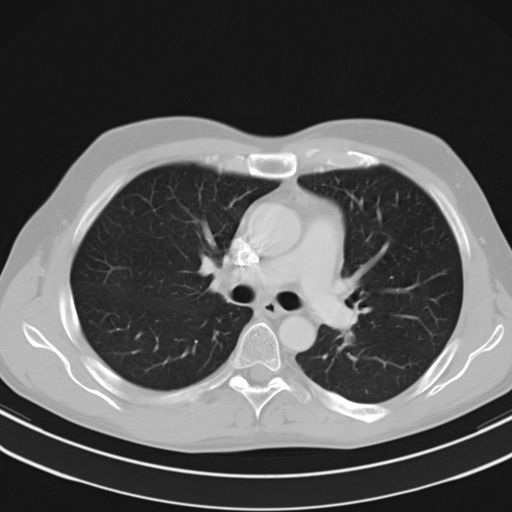

CT-scan van de thorax

CT-thorax

Hier wordt een beeld gevormd van de structuren van de borstkas. De longen, het mediastinum maar ook de bloedvaten en het hart worden beoordeeld. Tijdens het onderzoek zal de patiëtn gevraagd worden om de adem in te houden. Dit om een egaal opvolging van de beelen te krijgen. Ook is het uiteraard van belang om tijdens het onderzoek niet te bewegen. Door de steeds toenemende snelheid van de toestellen is dit echter niet een zware opdracht. Als je denkt dat een volledig longscan ongeveer een kleine dertig seconen in beslag neemt. Het kan echter zijn dat er volledigheidshalve een tweede opname wordt genomen, blijven liggen tot men u zegt dat het afgelopen is, is dus wel da boodschap.

Afhankelijk van de indicatie wordt er al dan niet besloten om contrast toe te dienen.

Ook hier is het dan nodig om de patiënt nuchter te houden ten minste vier uur voor het onderzoek.